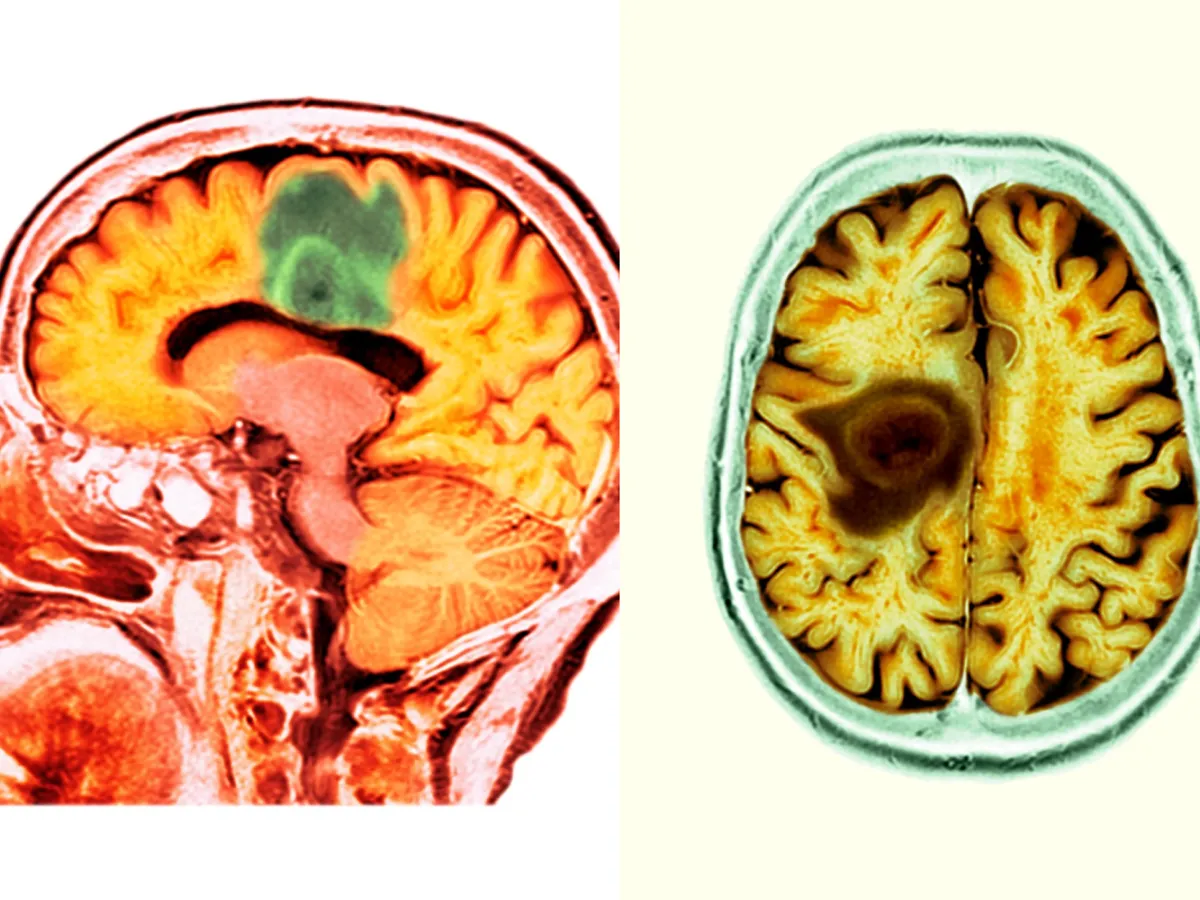

Bărbatul a fost diagnosticat cu glioblastom - un tip agresiv și terminal de cancer cerebral

După ce am fost diagnosticat cu glioblastom, un tip agresiv și terminal de cancer cerebral, tricotatul a devenit o modalitate de a-mi ține mâinile ocupate și mintea calmă. În timp ce mă recuperam după o operație pe creier și treceam prin șase săptămâni de radioterapie zilnică, am tricotat zeci de cârpe de vase simple din bumbac pentru prietenii și familia mea pentru a le mulțumi pentru sprijinul lor. Fiecare dintre ele a durat doar câteva ore, dar fiecare cusătură m-a făcut să mă simt conectată emoțional cu cei care au avut grijă de mine.